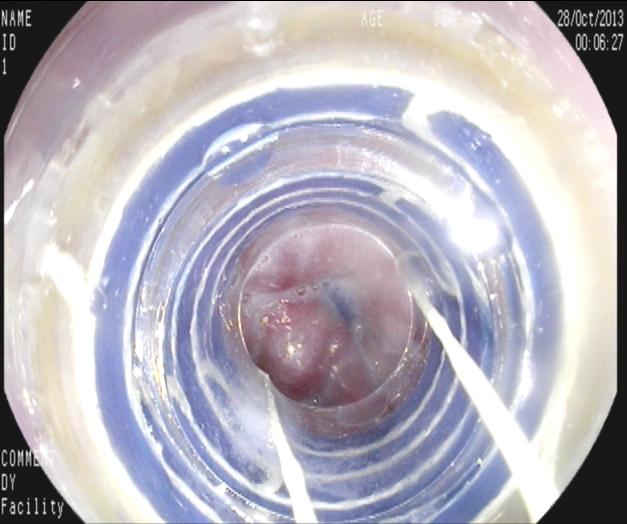

上2圖為套扎治療過(guò)程中。

【二次套扎】

患者治療后15 天后2013-11-13復(fù)查,尚有段狀曲張?jiān)俅翁自委煛?/span>